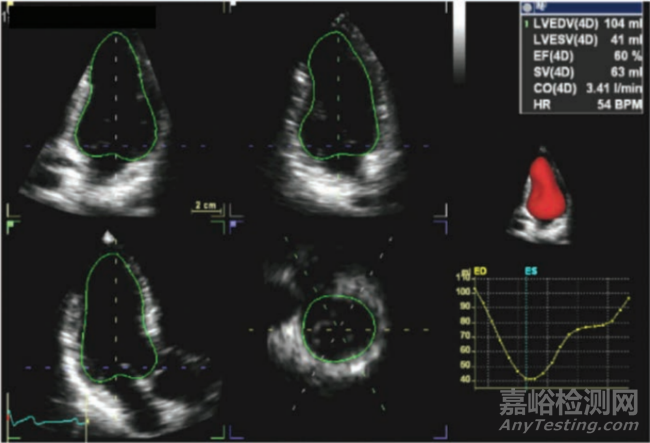

圖12:自由呼吸條件下采集的CMR圖像。圖片引自參考文獻(xiàn)9

心肌組織特性顯像一直是CMR的強(qiáng)項(xiàng),同時(shí)也是準(zhǔn)確量化評估因缺血造成心肌損害的范圍和程度、提示預(yù)后風(fēng)險(xiǎn)的重要技術(shù)手段[10,11]。T1 mapping技術(shù)是無創(chuàng)評估心肌組織特性的新型技術(shù),近年來逐步開始在臨床推廣。通過心臟增強(qiáng)前初始T1值(Native T1)、增強(qiáng)后T1值(Enhanced T1)以及細(xì)胞外容積分?jǐn)?shù)(extracellular volume fraction,ECV)來無創(chuàng)地評估由于纖維化引起的T1值的改變,T1 mapping可定量評估心肌梗死損傷的動態(tài)變化,無創(chuàng)地監(jiān)測組織損傷的演變,也為心肌纖維化的定量評估以及心衰風(fēng)險(xiǎn)預(yù)測提供重要手段。在一定程度上可以成為心肌延遲強(qiáng)化(LGE)在心肌纖維化和肥厚性心肌病(HCM)評估方面的補(bǔ)充和替代,如下圖13所示。T2 mapping技術(shù)是通過測量心肌組織橫向弛豫時(shí)間(T2值)來對心肌水腫進(jìn)行評估的定量技術(shù)。心肌水腫是包括心肌炎和心肌梗死在內(nèi)的多種心肌疾病的重要指征。T2 Mapping技術(shù)正逐步取代傳統(tǒng)的T2加權(quán)成像技術(shù),成為相關(guān)適用癥的優(yōu)選診斷手段。T2* mapping通過對組織T2*弛豫時(shí)間成像,間接反映不同組織器官間的鐵含量情況,實(shí)現(xiàn)對心肌組織鐵代謝的監(jiān)測評估,指導(dǎo)鐵螯合治療。近期多個(gè)臨床研究表明,T2*異常與心肌纖維化、心肌梗死后的微血管損失都有一定的相關(guān)性,因此對于心衰以及急性心肌梗死的評估預(yù)后也有一定的臨床價(jià)值。

圖13:LGE延遲強(qiáng)化顯像與T1 Map ECV顯像的三個(gè)對比示例。圖片引自參考文獻(xiàn)[11]